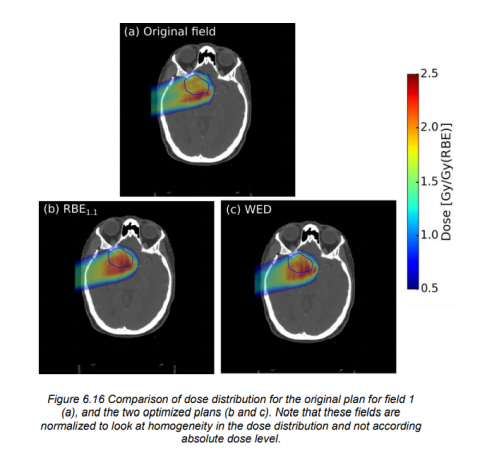

Her har vi undersøkt korleis variasjon i den relative biologisk effektiviteten (RBE) til protonterapi påverkar behandling av barnekreft og hovud- halskreft.

I klinisk praksis reknar ein at protonterapi er 10% meir effektiv enn konvensjonell strålebehandling med foton. Med andre ord er den relative biologiske effekten (RBE) til proton lik 1,1. Eigentleg er samanhengen i biologisk effekt meir kompleks enn som så, og dette er tema for eit pågåande forskingssamarbeid med Universitetet i Bergen.

RBE er ikkje konstant, men avhenger av både biologiske faktorar som celle- og vevstype, fysiske faktorar som ionisasjonstetthet og også kva endepunkt ein brukar for å ‘måle’ biologisk effekt. Ionisasjonstettheten – på engelsk linear energy transfer (LET) – varierer langs strålebanen og er høgst for låge protonenergiar, altså i det partikkelen stoppar opp. Dette er ein medverkande faktor for at ein med protonterapi unngår stråleretningar der kritiske risikoorgan ligg rett bak (distalt) for målvolumet; ein er bekymra for at høgare LET i dette området kan medføre større risiko for biverknader. Ved hjelp av såkalla Monte Carlo simuleringar kan ein rekne ut nøyaktige kart for LET i pasienten, og saman med kliniske data kan ein bruke dette til å lære meir om dei biologiske effektane av protonterapi. Endepunkt målt med celledata (in vitro) vert vanlegvis nytta i utvikling av fenomenologiske modellar som er meir sofistikerte i estimering av RBE enn det som vert nytta klinisk. Det er i dag stor usikkerheit i estimering av dei faktiske biologiske effektane til protonterapi relativt til konvensjonell strålebehandling med foton.

I dette prosjektet som er leia av Kristian Ytre-Hauge ved Institutt for fysikk, UiB, utviklar ein modellar for estimering av RBE, samt Monte Carlo verktøy for å kunne estimere LET og RBE i pasientar som har fått behandling med protonterapi i utlandet, blant anna i Jacksonville i Florida i USA.